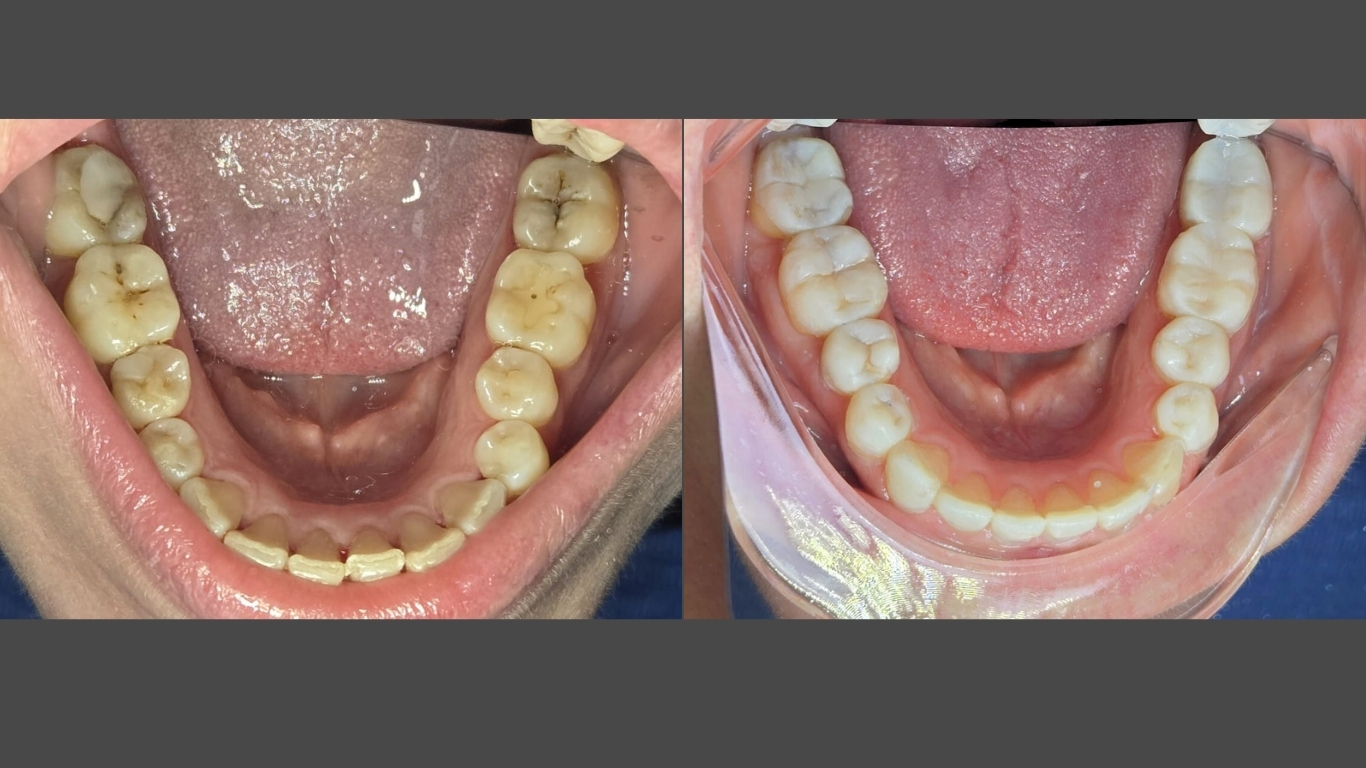

Caso Clínico 1